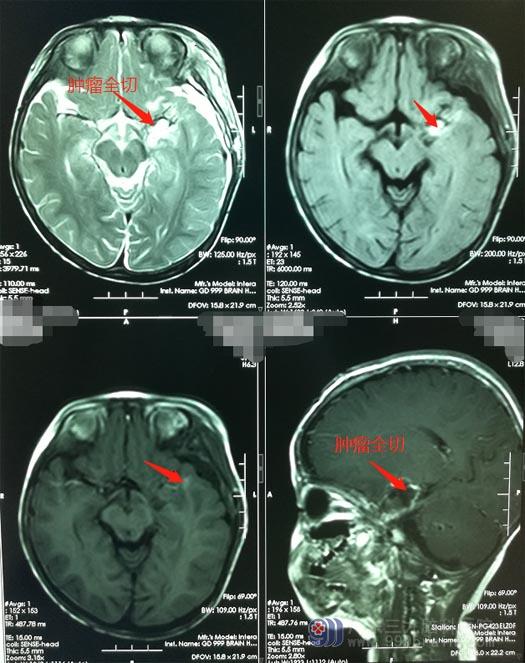

小雪父母也一致同意手术治疗。医院副院长、神经外五科主任鲁明带领团队在全麻下为小雪施行“左侧翼点入路行左侧颞叶内侧胶质瘤切除术”,术程顺利,镜下将肿瘤全部切除。

手术后的小雪神志清楚,生命体征平稳,未出现癫痫发作,能够自主活动。复查头颅CT见原肿瘤已切除,术区未见出血,目前正在继续康复治疗。